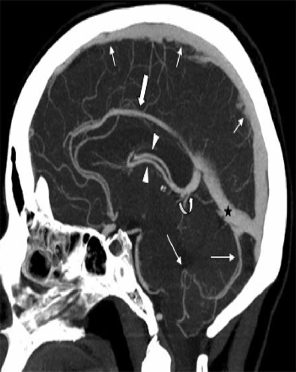

Computed Tomographic Cerebral Venography (CTV)

Can be reliably assess intracranial venous system

Comparable to MR angiographic techniques Rapid and readily available

Using iodinated contrast material